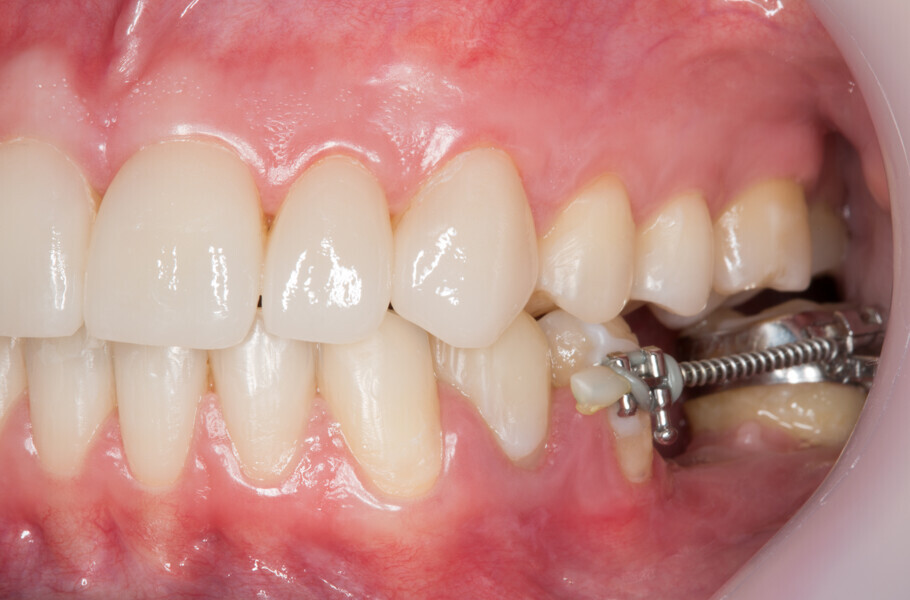

Fig. 2: Initial clinical situation.